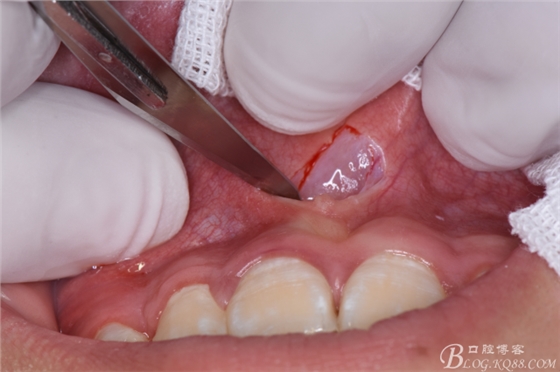

圖8.先拔除11、21之間多生牙,做唇側(cè)弧形切口

圖9.翻瓣、暴露唇側(cè)骨面,高速渦輪機去骨。